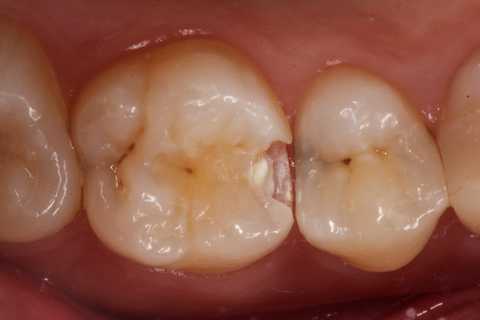

クラックが気になるのだが、象牙質には広がっていないようだったので、このまま充填した。

では時系列でどうぞ

鏡像、クラック部分は拡大した。